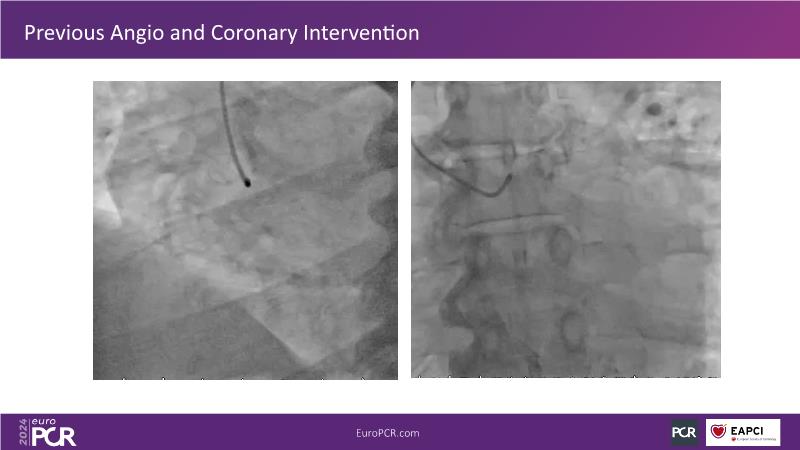

Physiology guided post-DCB treatment to safely limit stenting. Validation in complex clinical settings with the optical Optowire III pressure guidewire

Follow this session to discover how accurate resting index can inform decision-making for DCB in CTO patients and understand the role of physiology in a new PCI workflow for complex MVD. Thus, you will learn about a DCB intention-to-treat strategy guided by post-PCI coronary physiology in complex lesions, review new procedural techniques and workflows from real-world cases, and explore the pros and cons of this novel approach.